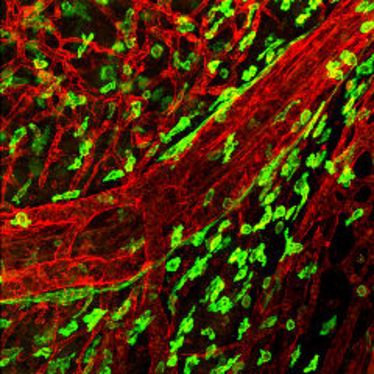

Verleihung des Pro Scientia Preises und Festvorträge der Preisträger Lydia Sorokin und Thomas Pap

Verleihung des Pro Scientia Preises und Festvorträge der Preisträger Lydia Sorokin und Thomas Pap

Vortrag des SFB 492: Extrazelluläre Matrix

Vortrag des SFB 492: Extrazelluläre Matrix